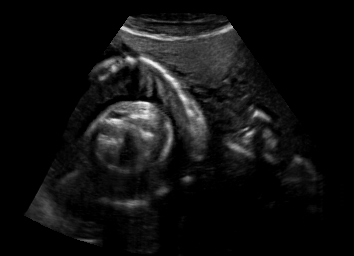

Real in-vivo images. 22 ultrasound sequences were collected using a GE Voluson E8 machine during standard fetal screening exams of 8 patients. Each sequence is several seconds long. We extracted all 4427 frames and resize them to , see Fig. 2 for some examples. The resulting image set was randomly split into training-validation-test sets by a 80-10-10% ratio.